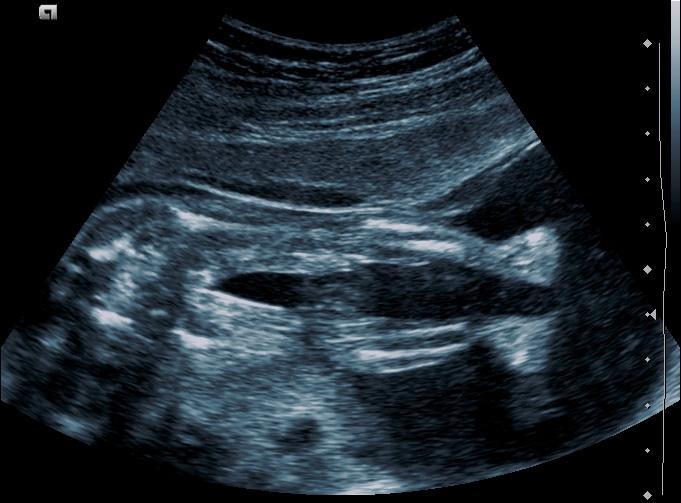

Optymalny wiek ciążowy dla pierwszego badania prenatalnego zawiera się między 11-13+6 tygodniem ciąży, długość ciemieniowo-siedzeniowa (CRL) musi się mieścić między 45 a 84 mm. Poza stwierdzeniem ciąży żywej, można określić jej dokładny wiek, stwierdzenie obecności dużych wad płodu, a w ciąży mnogiej ocena ilości płodów, kosmówkowości.